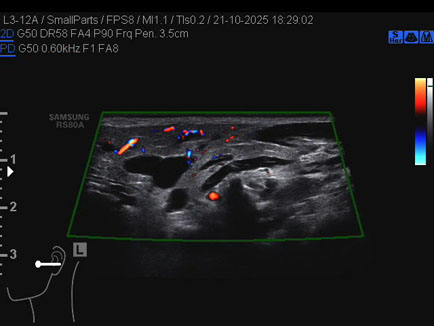

Ecografia del: 21/10/2025

Strumento: Samsung

Sonda: Lineare

Età Paziente: 50 anni

Commento all'esame: 50enne con stenosi del dotto di Stenone sn ed ectasia del dotto medesimo a dx.

Conclusioni: stenosi del dotto di Stenone sinistro (left Stensen's duct stenosis).